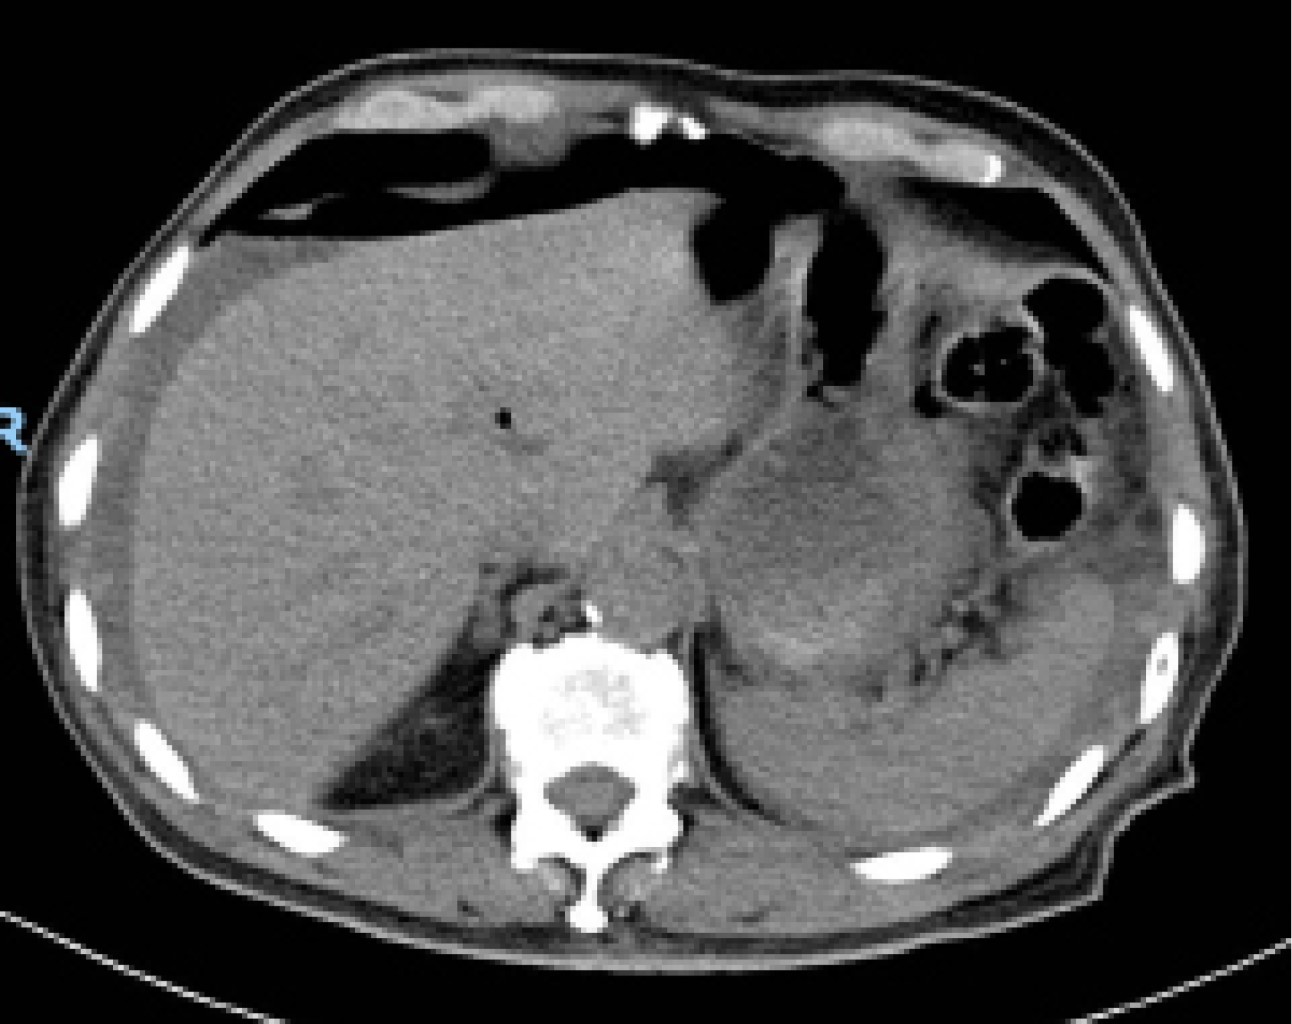

Se realizó ultrasonido de abdomen total reportando líquido libre perihepático, periesplénico y en hueco pélvico, por lo que se solicitó tomografía axial computarizada (TAC) de abdomen en la que se observó abundante líquido libre, neumoperitoneo (Figura 1) y hernia inguinal bilateral con contenido epiploico en la izquierda.

Figura 1